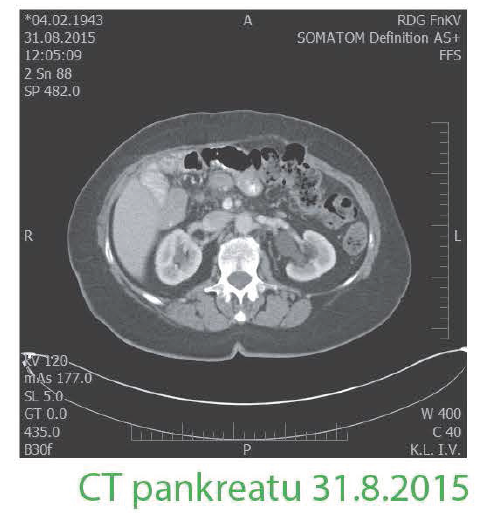

Poslední restaging

8/2015 bez známek diseminace či recidivy v oblasti odstraněných metastáz, pacientka ve výborném klinickém stavu bez neurologických či kognitivních poruch, bez dýchacích obtíží, zažívání prakticky bez komplikací ECOG 0-1